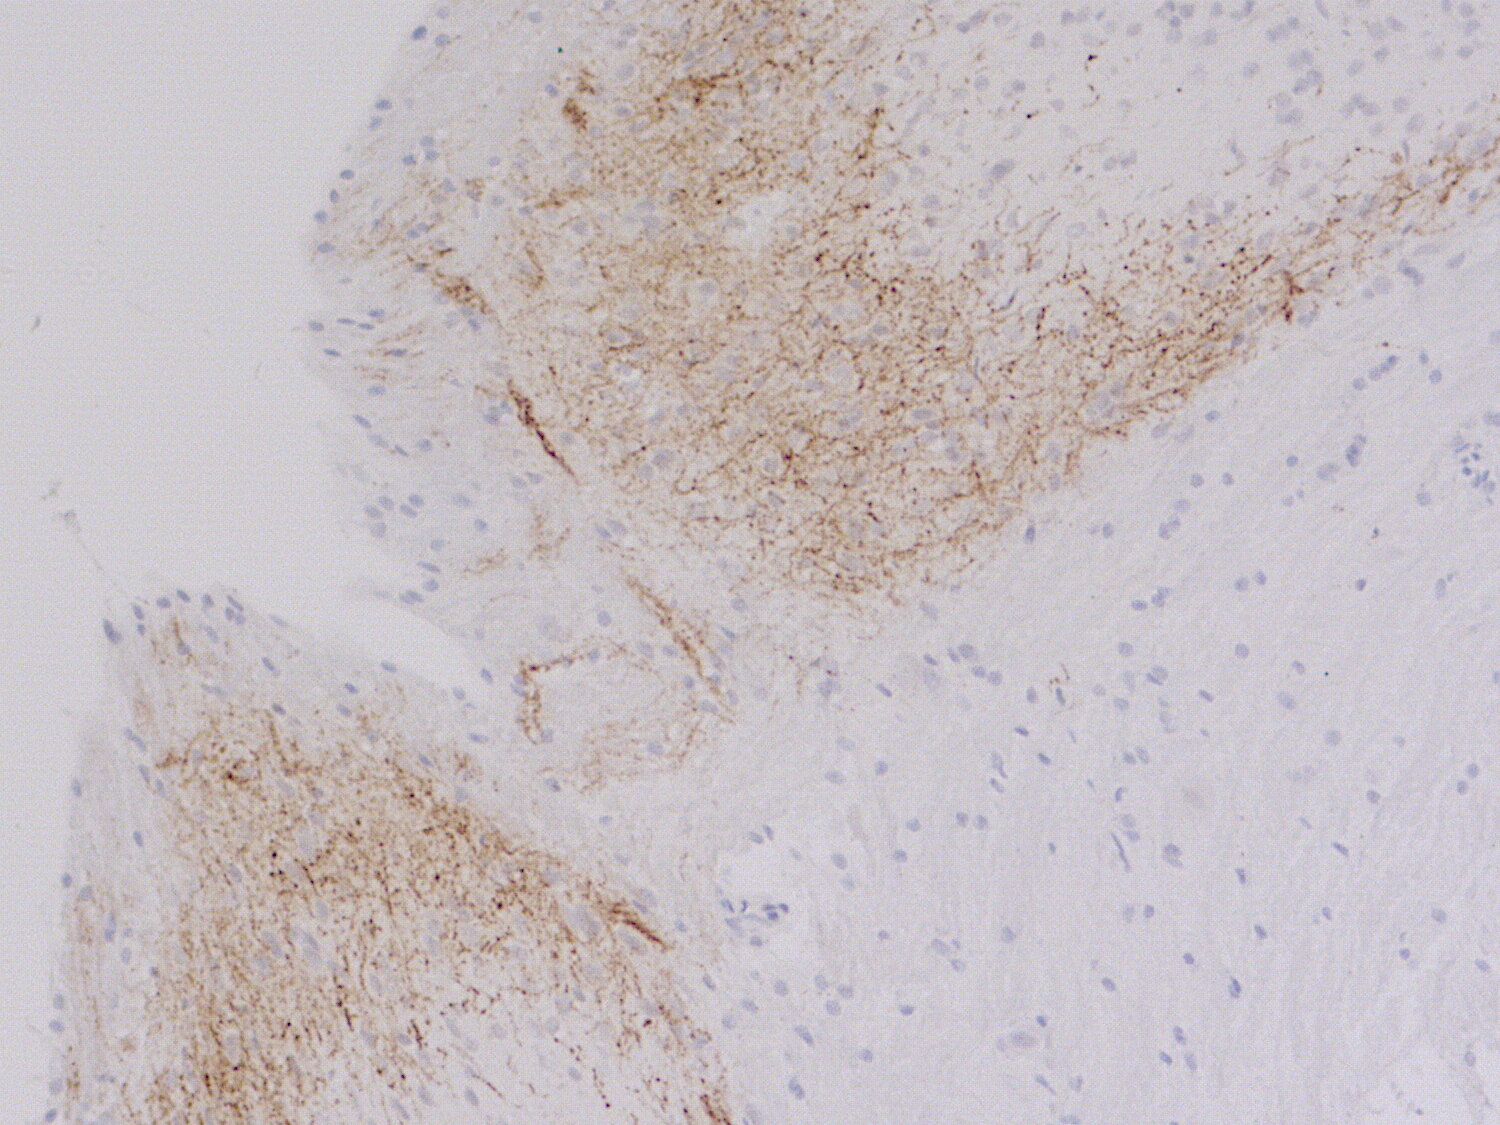

Calcitonin gene-related peptide (CGRP) is a 37-amino acid peptide produced by alternative splicing of calcitonin gene transcripts. It is characterized by a six amino acid ring structure linked by a disulfide bridge and an amidated C-terminus.

CGRP is present in parafollicular cells (C-cells) of the thyroid and in central and peripheral nerves. It is a potent vasodilator and can function in the transmission of pain. It has a major role in migraine pathophysiology, and CGRP antibodies have been used successfully in immunoneutralization.